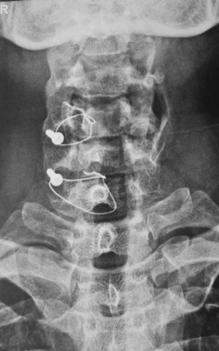

c0 c1 c2 fixation

c1 c2